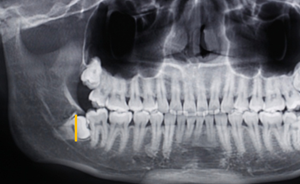

第二:充分暴露牙體組織后,沿47牙長軸方向?qū)?8進(jìn)行分冠,分冠線如下:

第三:分冠后近中牙體組織若無法順利脫位,可進(jìn)一步將近中牙冠分為頰舌兩部分,依次脫位。

![[頜面外科] 趙吉宏教授教你分析阻生牙阻力及畫分冠線 [頜面外科] 趙吉宏教授教你分析阻生牙阻力及畫分冠線](/UploadFiles/FCK/2018-06/6366416349545042977302140.png)